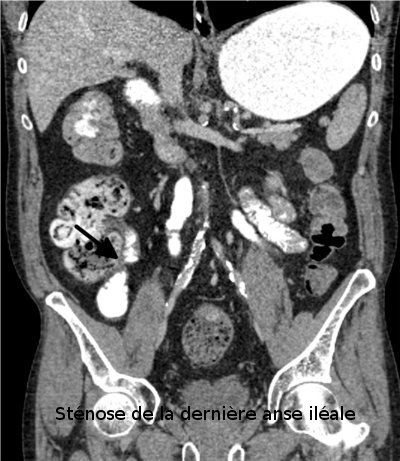

Son indication est essentiellement le diagnostic d'un cancer colorectal et de polypes, il est proposé en alternative à la coloscopie devant des symptômes évoquant un cancer colique, en particulier chez les sujets âgés ou fragiles pour lesquels il est préférable de se dispenser d'une anesthésie générale en première intention. Cette technique permet de faire le diagnostic du cancer et le bilan complet de recherche d'une métastase, en particulier hépatique ou pulmonaire.